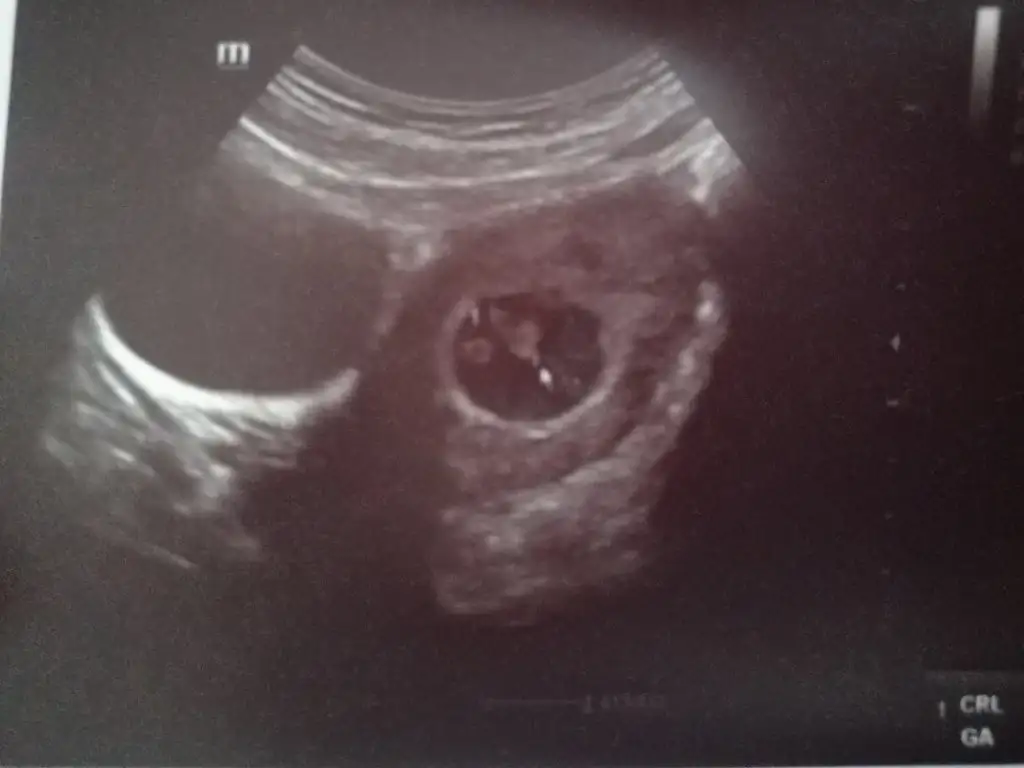

Bende duydum onu arastirip dogru cikanda var yanilma payida varramzi teorisini bileniniz var mı? ilk haftalardaki ultrason görüntüsünden cinsiyet tahmini yapılıyor

bebegin kesedeki yerine göre tahmin yapılıyor canım soldaysa erkek sağdaysa kız sanırımSen biliyor musun![]()

Hiç duymadım. Nasıl oluyor o.ramzi teorisini bileniniz var mı? ilk haftalardaki ultrason görüntüsünden cinsiyet tahmini yapılıyor

Şimdi ilk kızımda ki ultrason kagıdı A baktim ama anlayamadımramzi teorisini bileniniz var mı? ilk haftalardaki ultrason görüntüsünden cinsiyet tahmini yapılıyor

Soldaysa kız sağdaysa erkek değilmiydi yaabebegin kesedeki yerine göre tahmin yapılıyor canım soldaysa erkek sağdaysa kız sanırım![]()

ramzi teorisini biliyor musunuz? belki de öyledir ben çok iyi bilmiyorumSoldaysa kız sağdaysa erkek değilmiydi yaabende devreler yandı

Benimki böyle duruyorbebegin kesedeki yerine göre tahmin yapılıyor canım soldaysa erkek sağdaysa kız sanırım![]()

bu teoriye göre erkek canımBenimki böyle duruyor![]()